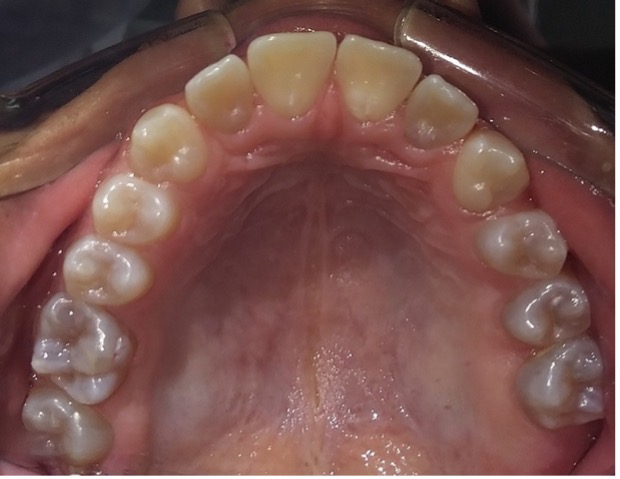

El examen clínico intraoral reveló alteración de la estructura y color de las piezas primarias, atrición y pérdida de la dimensión vertical (Figura 2). Radiográficamente se observó la presencia de coronas con marcada constricción cervical y raíces cortas (Figura 3). Presentaba alto riesgo cariogénico, por la presencia de lesiones de caries activas y dos restos radiculares, sumado a la anomalía estructural de la dentina (riesgo biológico específico) y bajo riesgo gingivoperiodontal. El riesgo socio-económico era alto por provenir de una familia con marcadas limitaciones económicas. Luego de la anamnesis, examen clínico y radiográfico, e interconsulta con el médico de cabecera se estableció el diagnóstico de DI Tipo I asociado a OI tipo I. Se planificó un tratamiento integral y preventivo con los objetivos de devolver forma y función, y proteger y evitar el desgaste de los tejidos conductas que pudieran interferir con el tratamiento.

Figura 2: Examen clínico intraoral del maxilar superior e inferior y vista anterior. Año 2007

En el último control realizado en el año 2018 (Figura 11) el paciente mantuvo el estado de salud logrado. El análisis cariogénico fue moderado (por su historia pasada de caries y su condición biológica específica) y el gingivoperiodontal bajo. El paciente continúa en atención en la COIN. Fue derivado en varias oportunidades al servicio de Ortodoncia de la Facultad de Odontología de la Universidad de Buenos Aires, pero hasta el momento no encaró ningún tratamiento propuesto.

Figura 11: Controles clínicos 2018

Cuando la dentición permanente está implicada, los incisivos inferiores son los más comprometidos, presentando en estos casos una coloración intensa propia de la DI (O’Connell, Marini 1999, Majorana, Bardellini et al. 2010, Petersen, Wetzel 1998), como se observa en el paciente. Las piezas permanentes fueron monitoreadas desde su erupción, recibieron protocolos preventivos con barnices fluorados, pastas y enjuagatorios fluorados domiciliarios, conjuntamente con un adecuado control de higiene oral.15